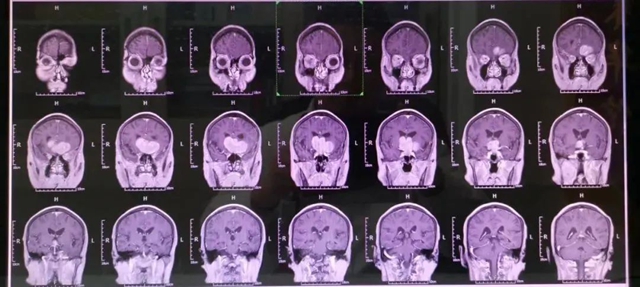

西南医科大学附属中医医院开设了“影像门诊”,满足广大患者对疾病影像学检查资料解读的需求。

精准解读与就医指引:专业医师为您深度解读影像报告,依据病情精准指导就医方向,让您不再对检查结果感到迷茫。

检查结果出现异常时,如MRI提示椎管、脊髓病变,需要专科医师进行专业评估;

疾病治疗后复查时,如肿瘤术后、脑梗死、关节韧带半月板损伤治疗后复查;

想要制定健康查体方案时,进行早癌筛查、胸部CT、颅脑MRI、腹部超声等检查;